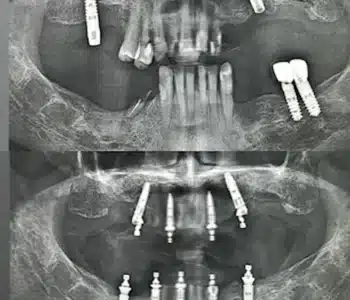

Dr. Seden Aksu is a specialist in modern implantology and surgical dentistry with extensive experience in the management of complex clinical cases. In her practice, she applies comprehensive surgical planning, minimally invasive techniques, and advanced regenerative technologies aimed at restoring both the function of the dentoalveolar system and the aesthetics of the smile. Dr. Aksu has significant experience in performing implant procedures, bone augmentation, and periodontal surgery, including the treatment of patients with severe bone loss. The primary goal of her work is to achieve stable, long-term outcomes in implant rehabilitation and the restoration of oral tissue health.